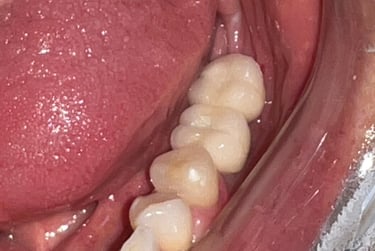

Aspecto clínico final - Imagens originais — nenhuma contém retoques

Caso da cirurgia guiada dispensando o enxerto - Imagens originais — nenhuma contém retoques